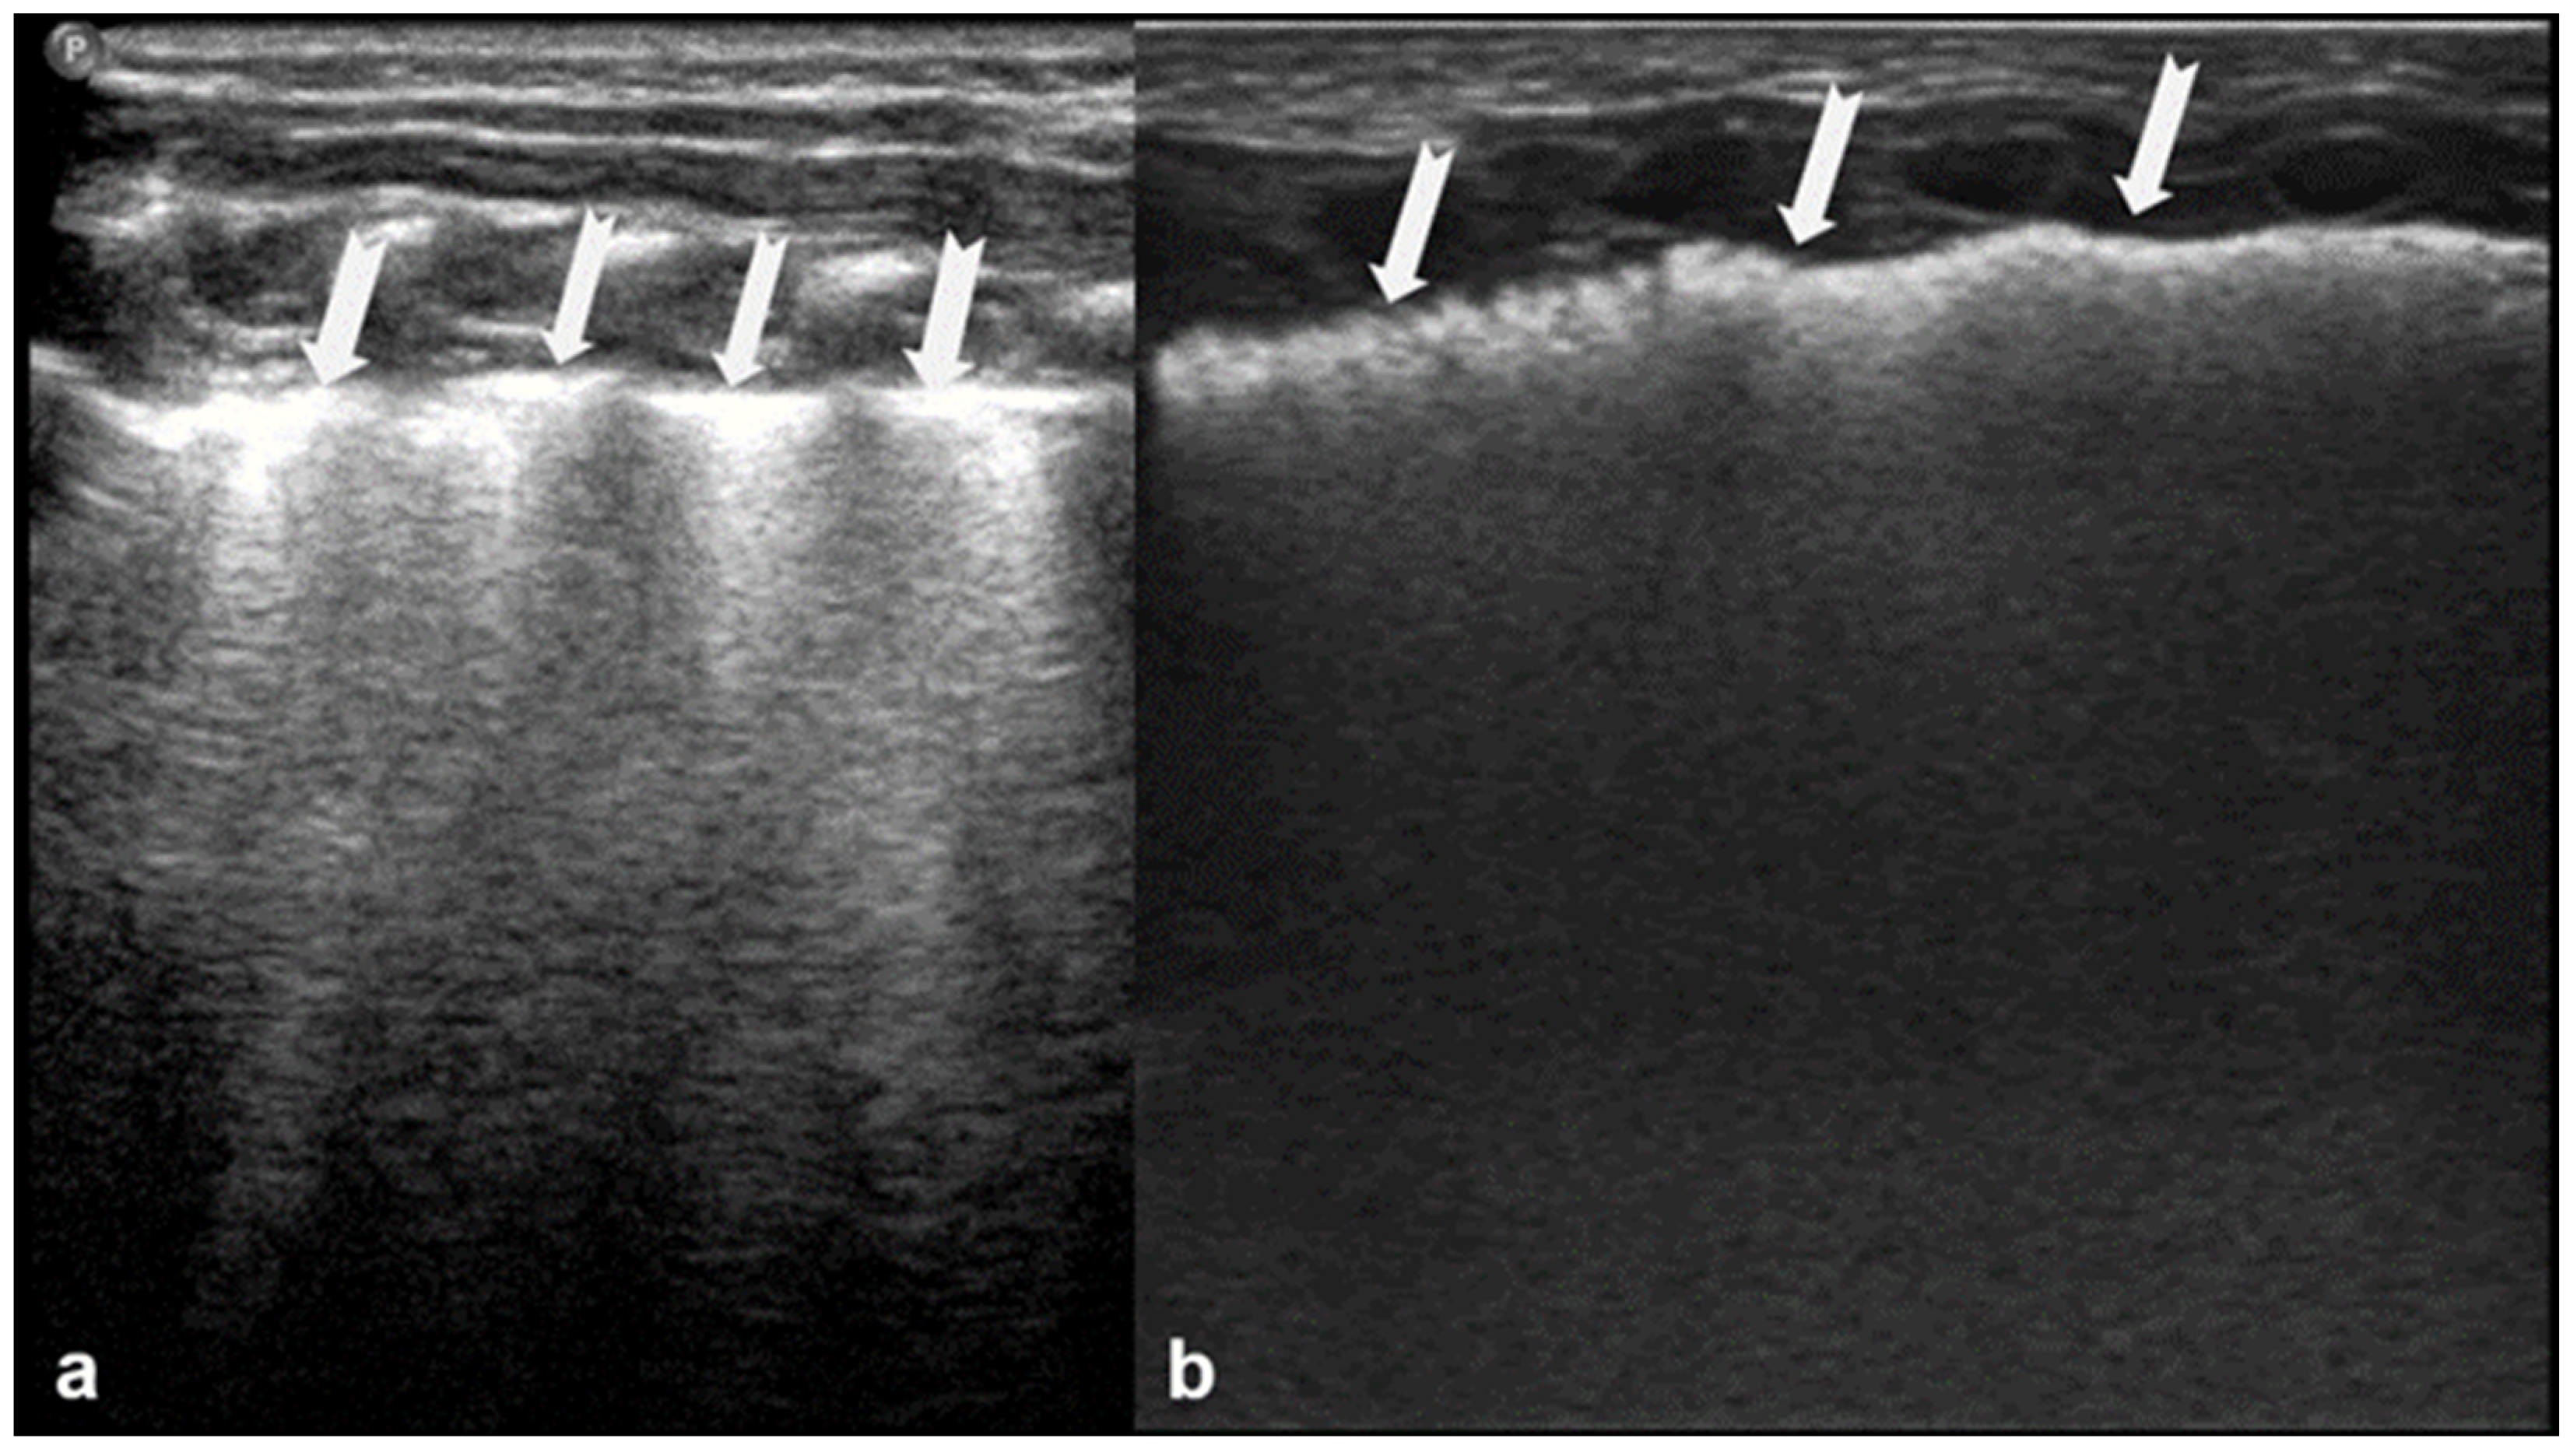

B-lines are vertical reverberation-like hyperechoic artifacts seen during LUS imaging which originate from the pleural line and extend to the bottom of the imaging field without fading in intensity (Figure 2a). B-line artifacts move in synchrony with lung sliding and intersect horizontal A-lines, effectively obscuring them. Their presence is typically associated with fluid accumulation in the alveoli or interstitial space, and they are commonly referred to as ultrasound lung comets. However, B-lines are frequently observed in neonates and can appear as a normal finding within the first 24 to 48 h after birth [13,14,17]. During LUS imaging, identification of up to two B-lines at the lung base is considered to be normal, while the presence of three or more B-lines between the intercostal space in a single view is considered significant and indicative of an underlying pathology. If multiple B-lines are identified by LUS, then the patient likely suffers from interstitial syndrome. When the air content in the lungs decreases, the number of lines tends to increase, because of the associated increase in lung density. Moreover, when the identified B-lines are confluent, this is an indication that the alveoli are filled with sub-pleural fluid. When interstitial edema is present, the presence or absence of B-lines can guide the administration of fluids [16,17,18,19]. However, it should be noted that B-lines are absent in the aforementioned pneumothorax.

Figure 2.

B-lines: Vertical reverberation-like hyperechoic artifacts originate from the pleural line and extend to the bottom of the image (a). This artifact could be normal (<3 in an intercostal space) or abnormal when are more than three, multiple or coalescent B-lines (b).

According to severity of the lung or interstitial pathology, B-lines may be solitary, few, multiple or even coalescent (Figure 2b), resulting in three imaging patterns associated with increasing severity: black lung, black and white lung, or white lung (Figure 3) [20,21].